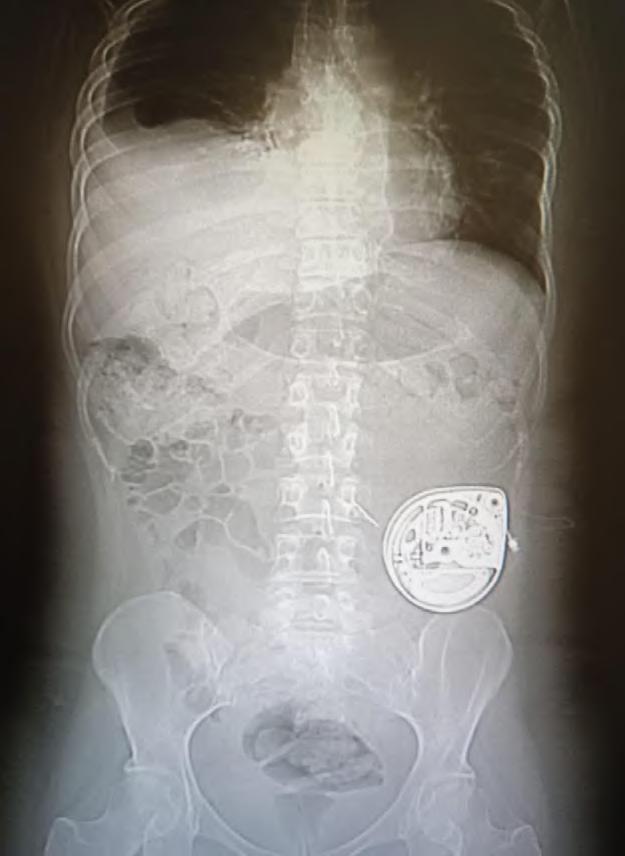

En agosto de 2025, Clínica Bupa Antofagasta realizó por primera vez en la región la implantación de una bomba de morfina intratecal, un dispositivo de alta tecnología que permite administrar el fármaco directamente en el sistema nervioso central para un control más efectivo y sostenido del dolor severo y refractario.

El procedimiento fue liderado por el Dr. Miguel Ángel Segovia, neurocirujano de columna con más de 12 años de trayectoria exclusiva en la clínica , junto al Dr. Fernando Maulén, anestesiólogo, en un equipo multidisciplinario que también incluyó a un cirujano general y otros anestesistas. La intervención, mínimamente invasiva, se aplicó a un paciente oncológico y consistió en la instalación subcutánea de un dispositivo que libera morfina de forma continua y ajustable en el espacio intratecal, reduciendo la necesidad de altas dosis orales y sus efectos secundarios.

«La medicina cuenta con escalones terapéuticos que se aplican de forma progresiva. Cuando las terapias conservadoras no logran controlar el dolor, existen excelentes alternativas quirúrgicas como esta, que no solo alivian el síntoma, sino que permiten reinsertar al paciente en su vida cotidiana y, sobre todo, recuperar su autonomía».

Uno de los principales beneficios de esta técnica es que los pacientes experimentan alivio inmediato, lo que en este caso permitió recuperar actividades cotidianas como levantarse, caminar o incluso pintar. El dispositivo, que funciona con batería, se implanta en el abdomen o la espalda y permite ajustar las dosis según las necesidades del paciente. La hospitalización asociada a este procedimiento suele ser breve, de no más de dos días, dependiendo de la evolución de cada caso.

Innovación y proyección

La intervención marca un precedente para el norte del país, ya que hasta ahora este tipo de procedimientos estaban mayoritariamente disponibles en Santiago, limitados por el alto costo de los equipos y la falta de infraestructura especializada.

Además, Clínica Bupa Antofagasta proyecta la apertura de su nueva Unidad del Dolor, orientada tanto a pacientes oncológicos como a quienes enfrentan enfermedades degenerativas, fibromialgia, artritis reumatoide y otras condiciones crónicas.

Según el estudio «Radiografía del Dolor en Chile», el dolor crónico afecta al 25% de la población general y a una de cada tres mujeres en el país, lo que refuerza la relevancia de contar con este tipo de alternativas avanzadas en la región.

«Como equipo y como clínica acercamos la medicina de primer nivel a la región. Todavía existe la percepción de que lo mejor está en Santiago, pero queremos dar una señal clara a las personas del norte: es posible acceder a medicina avanzada sin tener que tomar un vuelo», señaló el especialista.

Este procedimiento abre una nueva alternativa terapéutica en el norte del país, y refleja el compromiso de Clínica Bupa Antofagasta por acercar medicina avanzada a las regiones, contribuyendo a un acceso más equitativo y de calidad para los pacientes.

DR. FERNANDO MAULÉN

Bomba programable colocada en el espesor del celular subcutáneo de la fosa ilíaca izquierda.